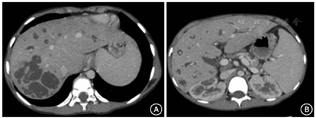

6例Caroli病患者中,影像学提示肾囊肿3例(50.0%)、肝囊肿2例(33.3%)、胆管结石3例(50.0%)、腹水0例、脾大2例(33.3%),6例行胃镜检查的患者均未发现食管静脉曲张。15例Caroli综合征患者中,影像学提示肾囊肿9例(60.0%)、肝囊肿8例(53.3%)、胆管结石5例(33.3%)、肝内胆管结石8例(53.3%)、腹水6例40.0%)、脾大7例(46.7%),15例行胃镜检查的患者中8例(53.3%)存在食管静脉曲张。21例Caroli病/Caroli综合征患者中未行肝穿刺活检的患者(8例),通过影像学诊断:CT可见肝内多发囊状或柱状低密度影,呈分支样扩张,与胆管相通,呈"囊尾征"或"蝌蚪征"(图1);MRI及磁共振胰胆管造影(MRCP)表现:可见扩张的小胆管悬挂在胆道树的枝头,形成"悬挂征"。部分还可见多囊肾、髓质海绵肾等肾脏囊性病变。

对于未行肝穿刺活检的患者,还可依赖于影像学检查进行诊断。腹部CT可发现囊状扩张的中央点状影,称为"中央斑点征",或囊状扩张的胆管与细小的胆管相通,形似蝌蚪,称之为"蝌蚪征"[9,10],对Caroli病提供准确的诊断。腹部MRCP平扫显示"悬挂征",囊状病变似悬挂在胆道"树"上的"果实"[11],提示Caroli综合征组常合并腹水、食管胃底静脉曲张、脾大等门静脉高压表现。有文献报道,MRCP对胆管扩张或狭窄的敏感性为90%~95%,对正常肝外胆管的显示率近100%,逐步成为首选的检查。但该病还需与梗阻性肝内胆管扩张、肝内胆管囊腺瘤、肝脓肿等疾病相鉴别[12]。